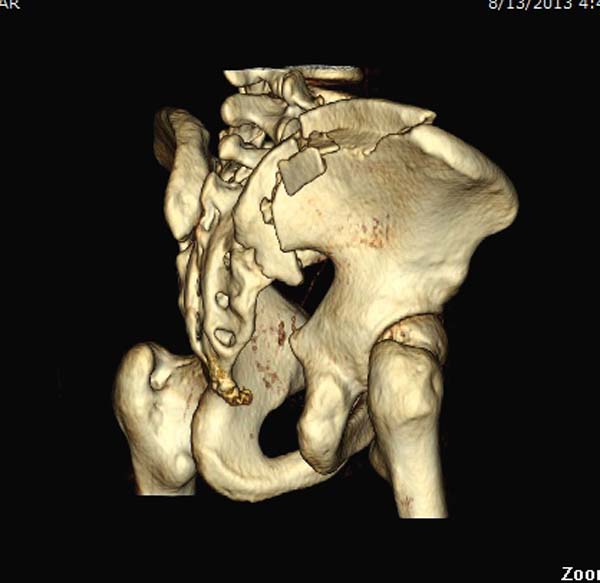

КТ, при детальном рассмотрении виден перелом задних отделов крыла подвздошной кости

KT